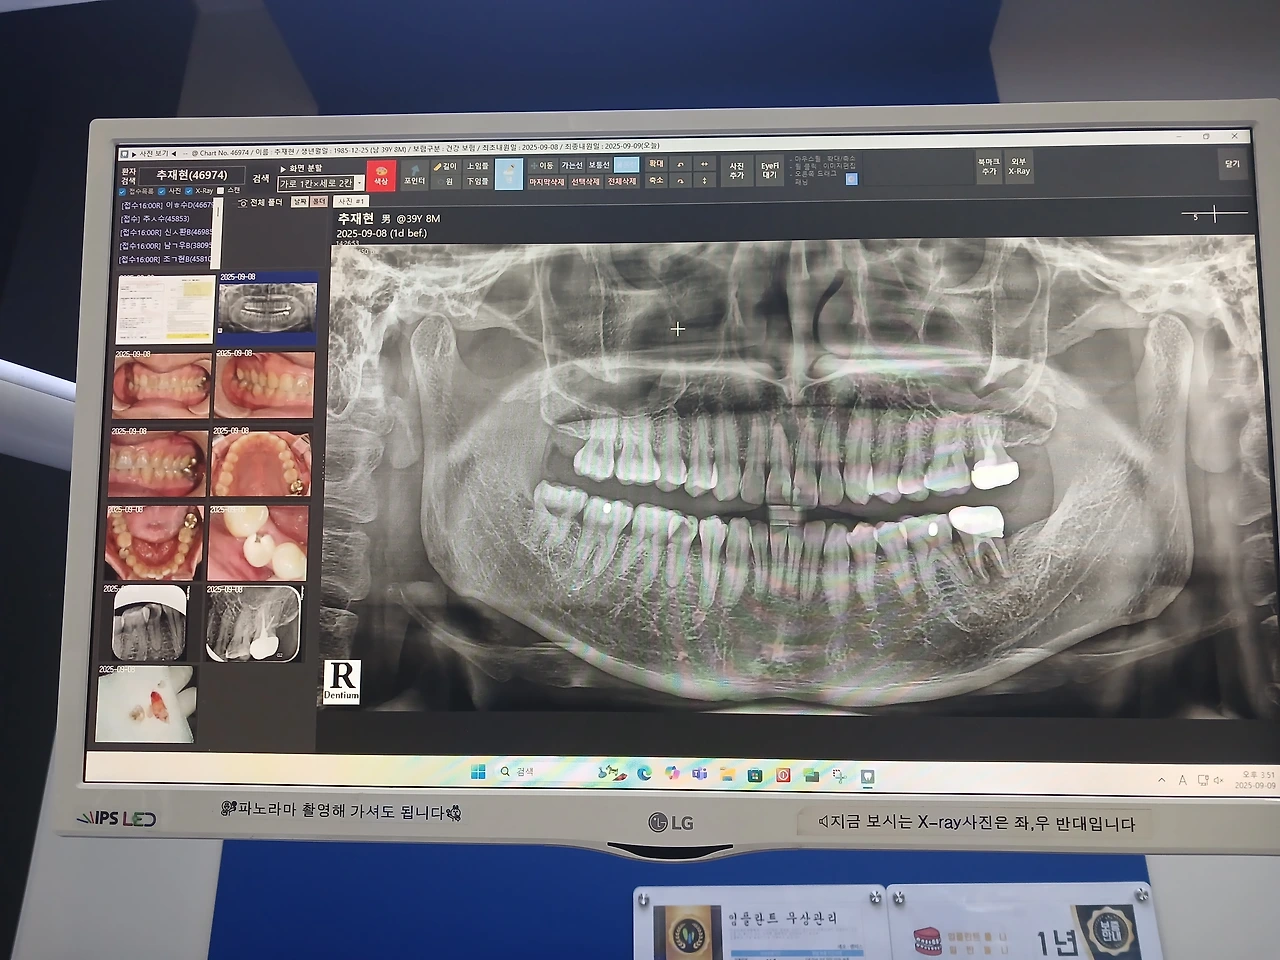

요즘은 후자 식사를 하고 있는데 세 남자들이 치아에 문제가 생기면서 전작과 후자의 절충한 식사로 술과 커피 인스턴트식품은 다시 안 먹게 되었다.

변화로는 치과신세를 자꾸 지게 되었다는 점

내 건강상식으로 스케일링은 한 번도 안 해주고 죽염소금물로 양치질을 해왔다.

안일하게 먹고 양치질을 제대로 하지 않아 치아가 상했지만 늦지 않았다.

원치 않았지만 어쩔 수 없다 여겨 스케일링을 하기로 결정을 했다.

처음 받아보니 가글로 마취는 했지만 보통일이 아니었다.

간호사님께서 좋은 기구와 실력으로 잘해주셨지만 기계 3대 정도의 다양한 소음과

전체이빨이 앞 뒤 갈려지는 느낌 치간제거하며 콕콕 쑤시는 걸 견뎌야 하는 시간..

다시는 스케일링하고 싶지가 않다.

어두운 누렁니를 감추려 의식적으로 환하게 웃지 못해 어정쩡한 미소를 지던 나에게

빛이 나는 하얀 치아가 생겨 자신 있는 웃음을 선물 받았다.

다시 스케일링을 받지 않고 치과신세를 지지 않는 꿈

깨끗한 치아를 유지하여 오랫동안 사용하는 경험의 기록을 만들어 간다.